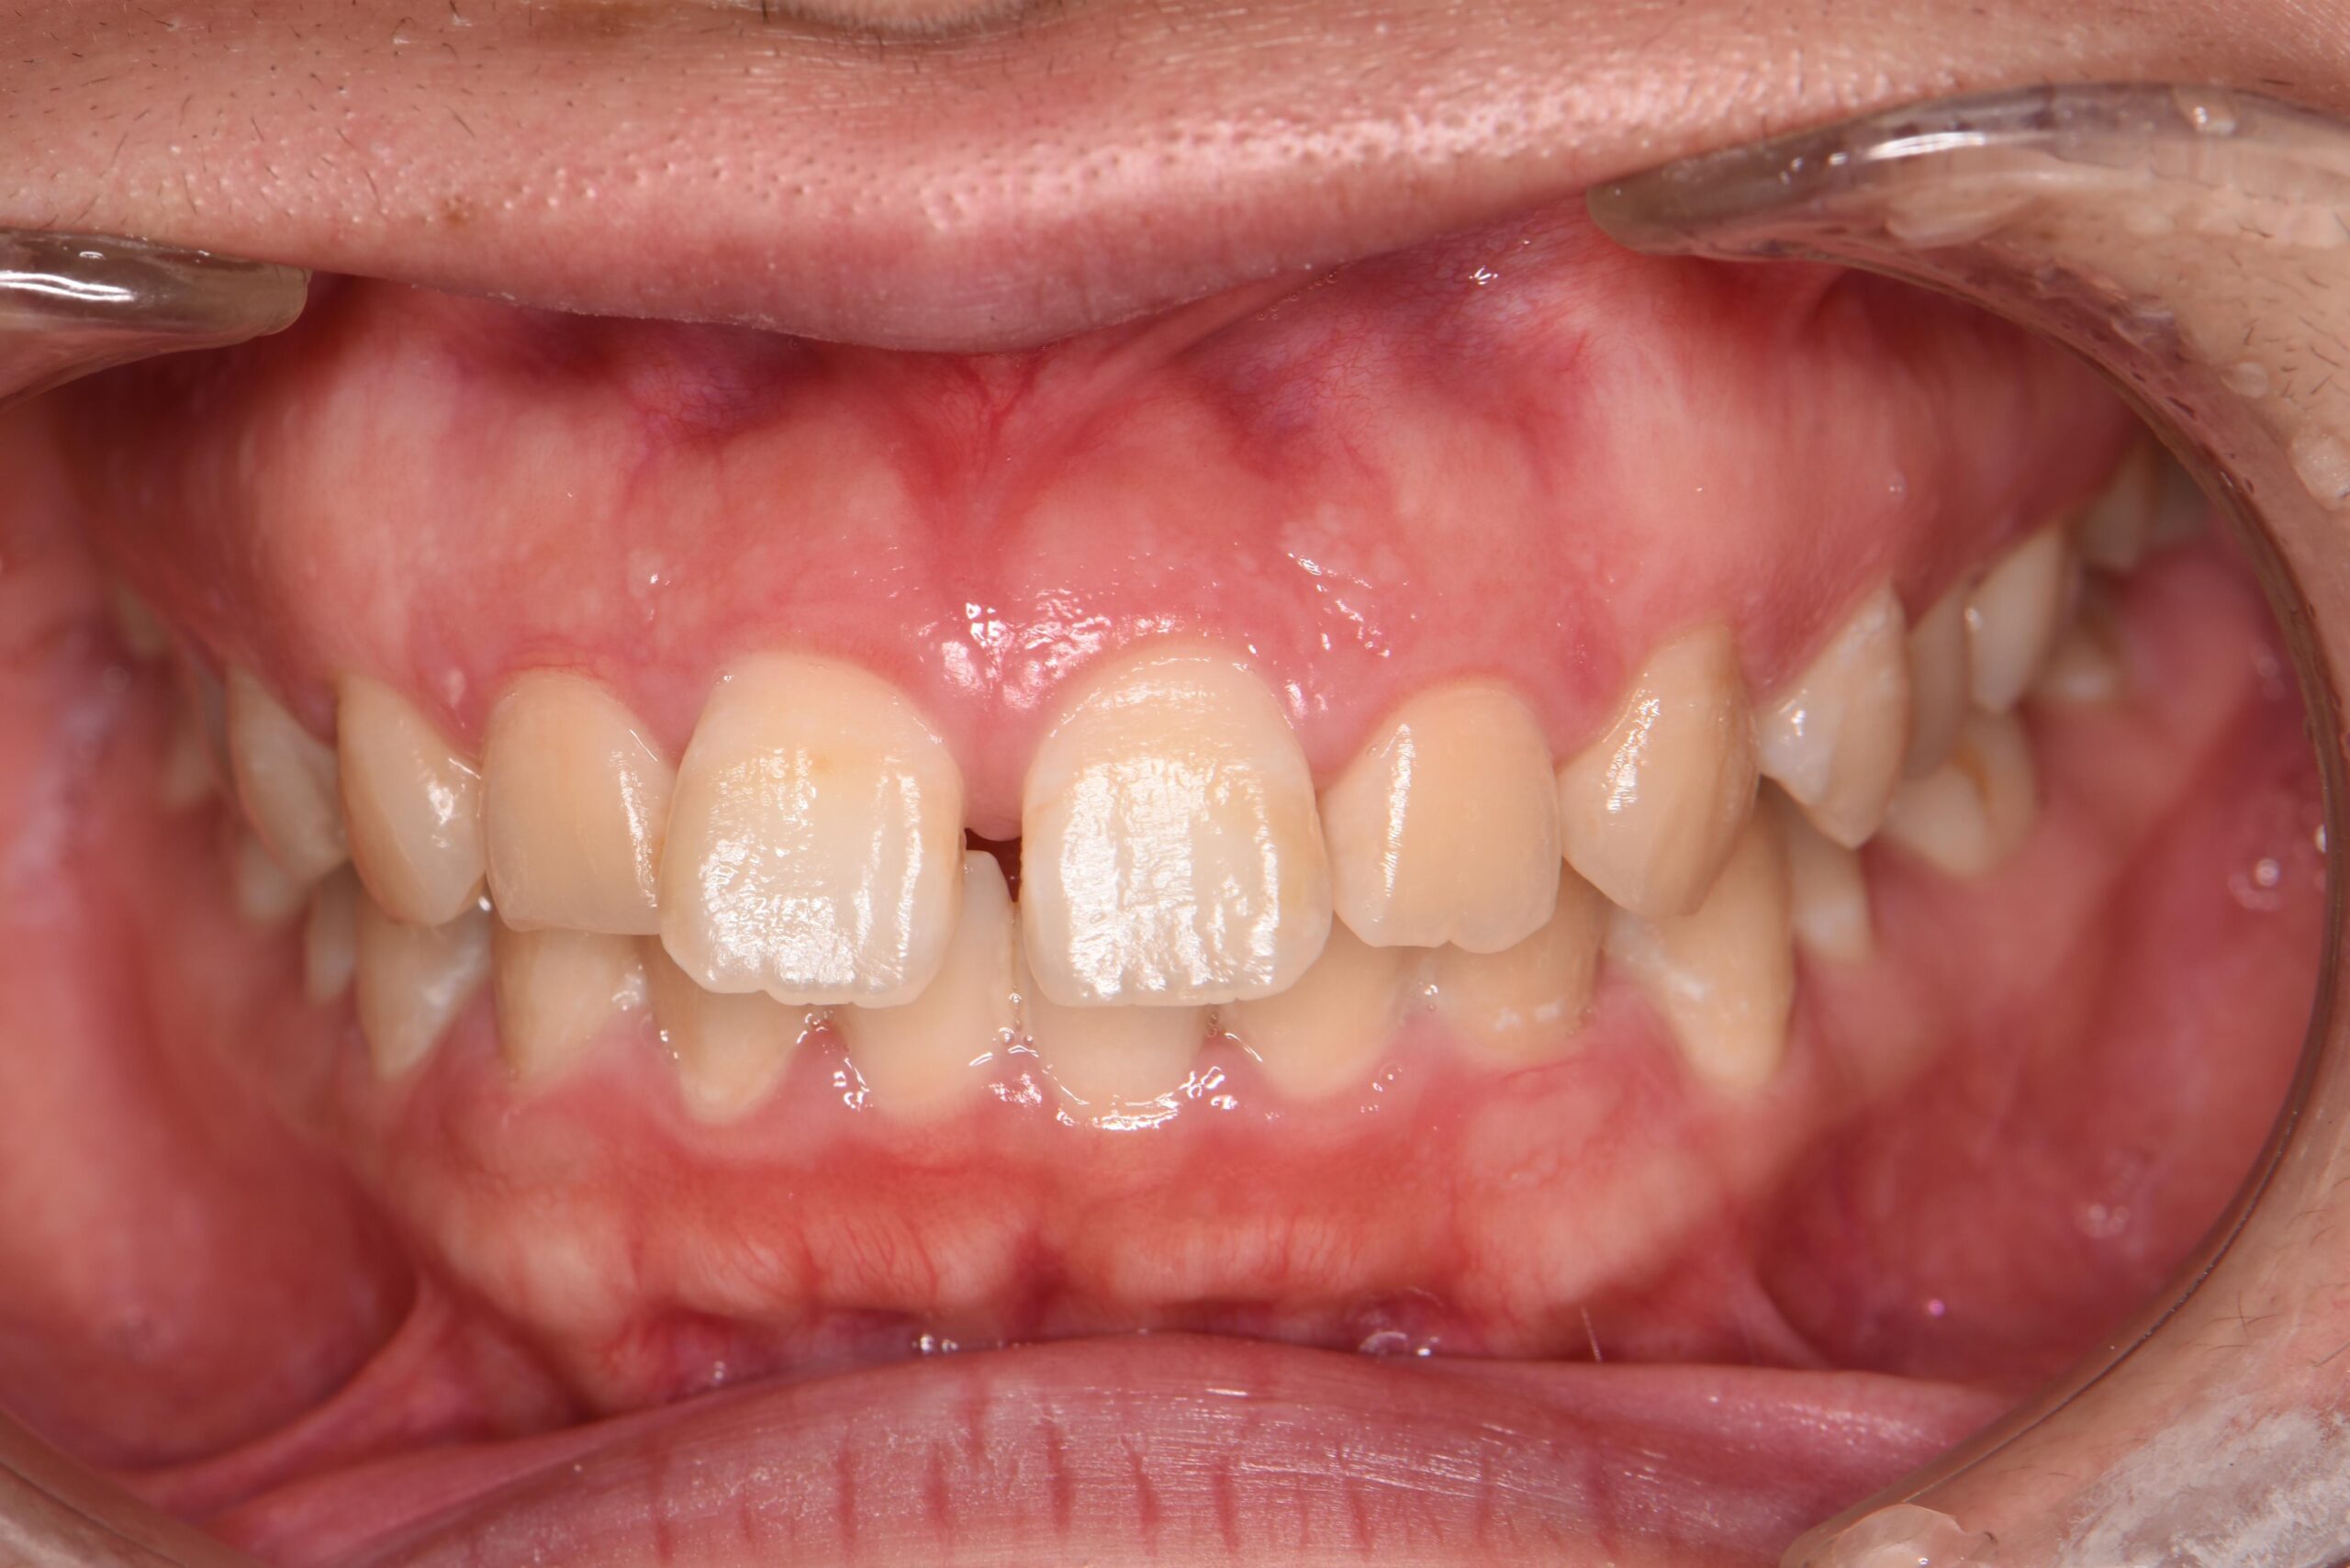

犬歯が外側に飛び出して、他の歯に重なっている状態です。八重歯は噛み合わせに問題が生じたり、歯磨きがしにくいことでむし歯や歯周病の原因となることがあります。